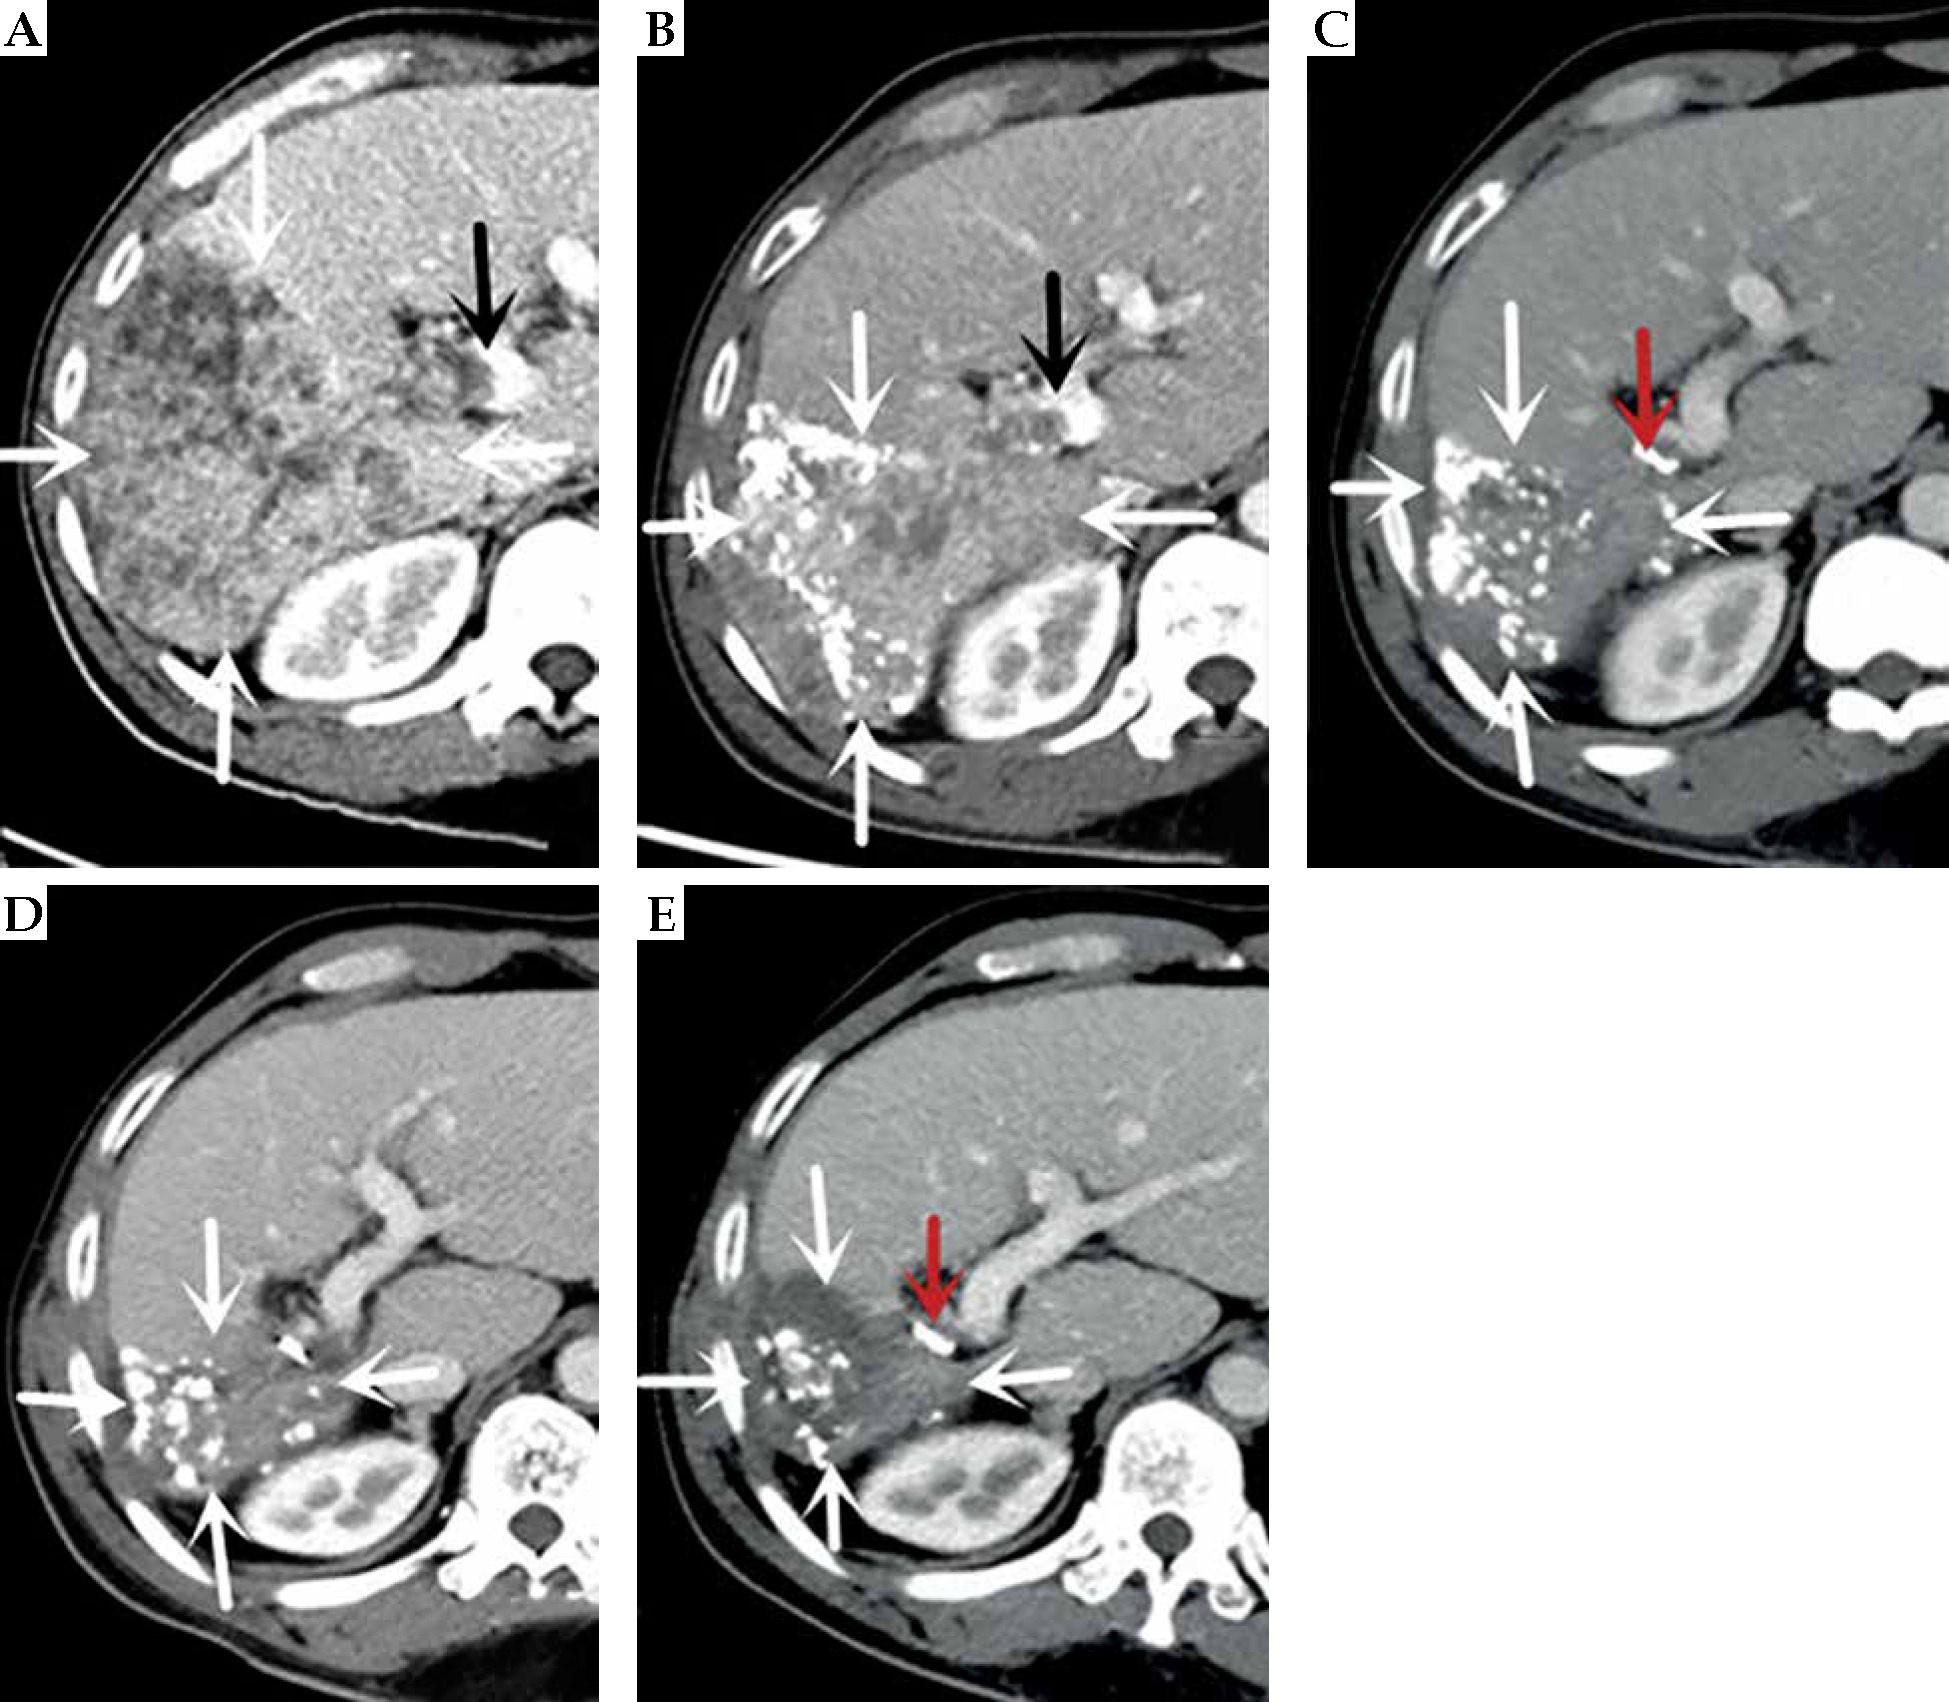

Fig. 2

Computed tomography (CT)-enhanced cross-sectional images of the portal phase before and after treatment. A) Before treatment. B) After more than 1 month of treatment. C) After more than 8 months of treatment. D) After more than 15 months of treatment. E) After more than 23 months of treatment. The white arrow indicate the gradually shrinking liver cancer lesion, the black arrow is the portal cancer thrombus, and the red arrow is the radioactive 125I particle

C-TACE was performed again on March 2, 2020, June 24, 2020, September 27, 2020, and December 17, 2020. The results of DSA hepatic arteriography showed that the right lobe of the liver was further reduced, and there was no arterio-venous fistula. The tumor-supplying artery was super-selected by microcatheter, and a chemotherapeutic solution was prepared by adding 50 mg of lobaplatin to 30 ml of 0.9% sodium chloride solution; chemotherapy was administering by infusion for 20 min via microcatheter. Pirarubicin 20 mg and iodized oil 10 ml was then used to prepare a suspension and embolized through the microcatheter, with additional gelatin sponge (diameter, 750-1,000 μm), until the tumor donor artery was completely embolized. The tumor was treated with oral anlotinib in a sequential manner. CT re-examination showed that the lesions in the liver gradually decreased, the portal vein gradually atrophied, a part of the portal vein opened, blood flow resumed, and the left lobe of the liver gradually increased. AFP level showed a continuous decrease (as of December 17, 2020).

On April 8, 2021 (after more than 15 months of treatment), the patient’s pain disappeared, NRS score was 3, his weight increased by 10 kg, and PS score was 0. CT results showed complete necrosis and no enhancement of the intra-hepatic lesion, atrophy of the portal vein, partial opening of the main trunk, and the right branch of the portal vein to restore blood flow (Figure 3). AFP level decreased to normal range (1.96 ng/ml). The patient returned to the hospital for follow-ups on July 28, 2021, December 26, 2021, July 25, 2022, and March 23, 2023, with no complaints of discomfort (PS score, 0). AFP values maintained within normal range, and CT results indicated no recurrence or metastasis. At the last follow-up on March 23, 2023, the patient had a pain NRS of 0, weight 68 kg, PS score 0, AFP 1.96 ng/ml, liver function Child-Pugh score 5 (human blood albumin 38 g/l, total bilirubin 6.2 μmol/l, PT 11.6 s, no ascites or hepatic encephalopathy). After extensive evaluation, the patient’s disease was completely controlled, with no long-term recurrence or metastases and radical outcome. To date, PFS is 37 months.